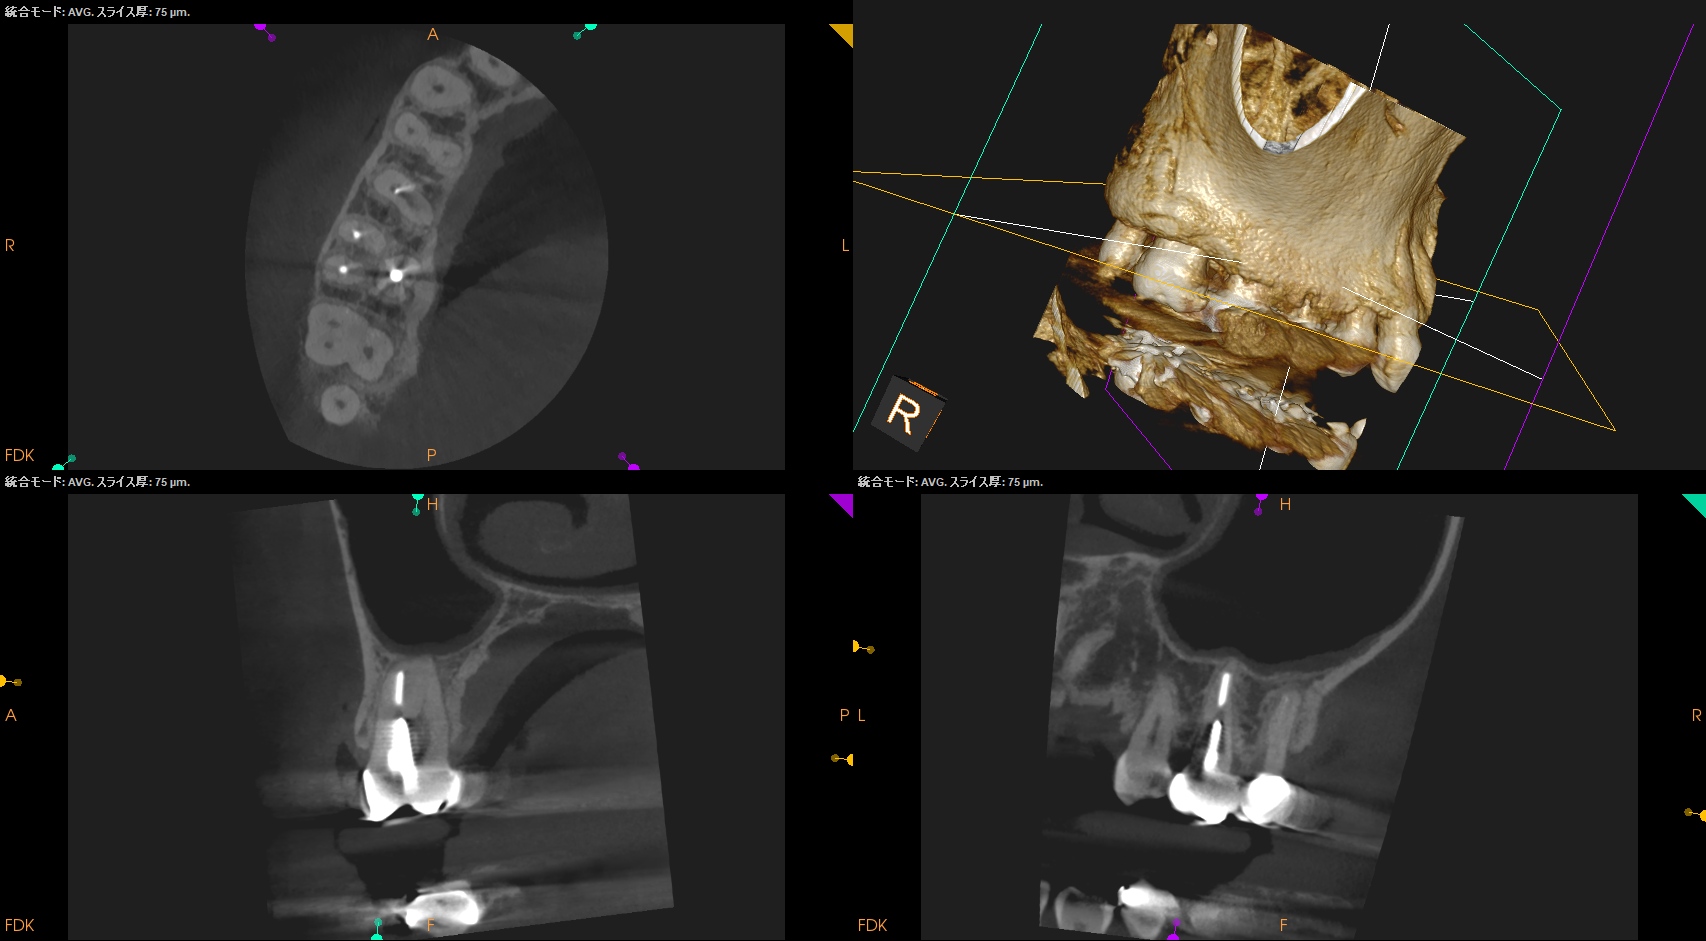

術後にPA, CBCTを撮影した。

問題はないだろう。

#3 MB Apicoectomy(2025.10.22)

CEJよりも10mm下方の#3 MBのApexをOsteotomyで探索する。

このApexから4mmの部分を想定しRoot resectionした。

今回は折れたFileごとMBのApexを除去した形だ。

この後メチレンブルーで染めて逆根管形成した。

逆根管充填した。